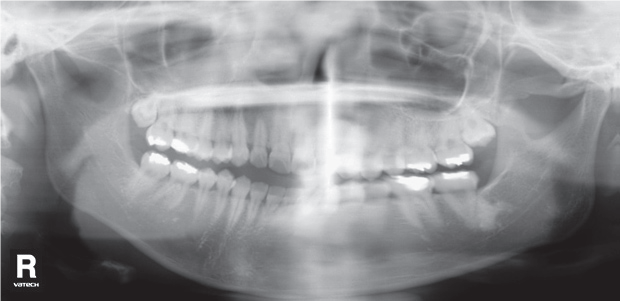

2. Наложение темной тени на верхушки зубов верхней челюсти.

Рис. 2. Наложение темной тени на верхушки зубов верхней челюсти.

Возникает за счет проекции воздуха в ротовой полости.

Что делать:

- Непосредственно перед началом экспозиции попросите пациента поднять кончик языка к нёбу.